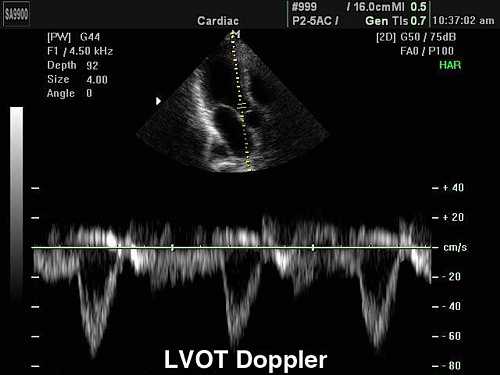

Если затруднена работа аортального протеза, скорость потока (следовательно, градиент давления) увеличивается, кроме случаев, если уменьшается сердечный выброс. Увеличение скорости потока через аортальный протез также можно ожидать при тяжелой протезной регургитации (следовательно, увеличения потока через аортальный протез). Однако, при аортальной обструкции (как при аортальном стенозе), при снижении фракции выброса левого желудочка, скорость потока ВТЛЖ может быть нормальной или слегка уменьшенной, и увеличивается при аортальной регургитации. Полезной для дифференциальной диагностики будет отношение средней скорости кровотока ВТЛЖ на протезе и интеграла линейной скорости кровотока. При повышении скорости потока через аортальный протез из-за обструкции протеза соотношение уменьшается, ≤0.2, а при повышении скорости из-за регургитации, соотношение остается нормальным, ≥0.3.

Допплеровская ЭхоКГ очень полезно для оценки функции протезного клапана:

- Препятствие кровотоку. Из-за того, что материал этих клапанов не соответствует требованиям, скорость потока через них отличается от обычных стандартных клапанов (см. Таблицу 6.1). Большинство протезов клапанов создают препятствия для кровотока. Можно произвести ряд измерений:

- Пиковая скорость. Она выше, чем в обычных клапанах, из-за относительно меньшей площади отверстия, обусловленной большим объемом искусственного материала. Пример диапазона приведены в таблице. Как правило, пиковая скорость> 2 м/с в МК обычно указывает на дисфункцию как механических, так и биологических протезных клапанов. Скорость потока в протезе аорты обычно

- Градиент давления (ΔP). Этот показатель рассчитывается по упрощенному уравнению Бернулли (ΔP = 4V2).

- Площадь отверстия клапана - измеряется по уравнению непрерывности